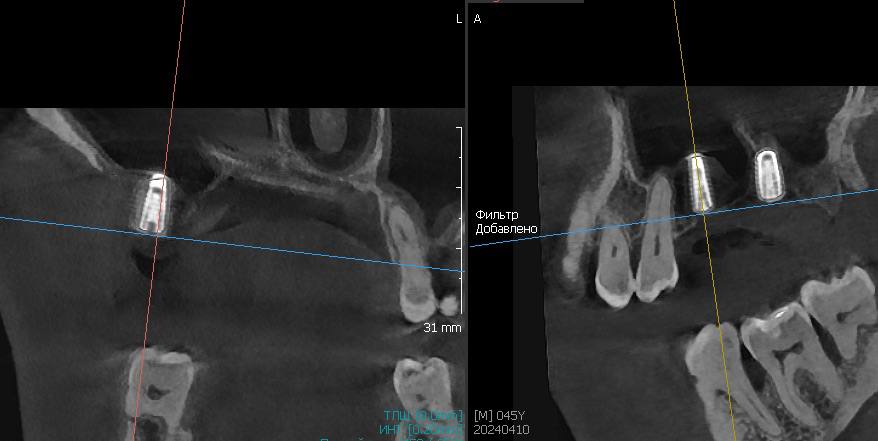

Открытый синус-лифтинг на губке и винте

Описание клинического случая:

• Открытый синус-лифтинг на губке и винте. Фиксация прямых мультиюнитов с усилием 30 Н/см

• После синус-лифтинга до установки имплантата прошло 3,5 месяца

Клинический случай Семерикова Дмитрия Юрьевича